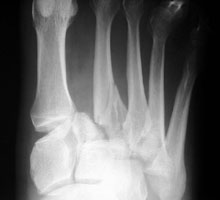

Lisfranc Fracture-Dislocation |

The Lisfranc fracture-dislocation is a term for the most common dislocation in the foot, consisting of dorsal dislocation of the tarsometatarsal joints. This entity is common in Charcot joints. Homolateral dislocation consists of lateral dislocation of metatarsals one through five or two through five. Divergent dislocation consists of lateral dislocation of metatarsals two through five and medial dislocation of metatarsal one. The injury is due to severe plantarflexion of the foot with folding of the midfoot upon the forefoot. This can be seen in parachute jumpers.